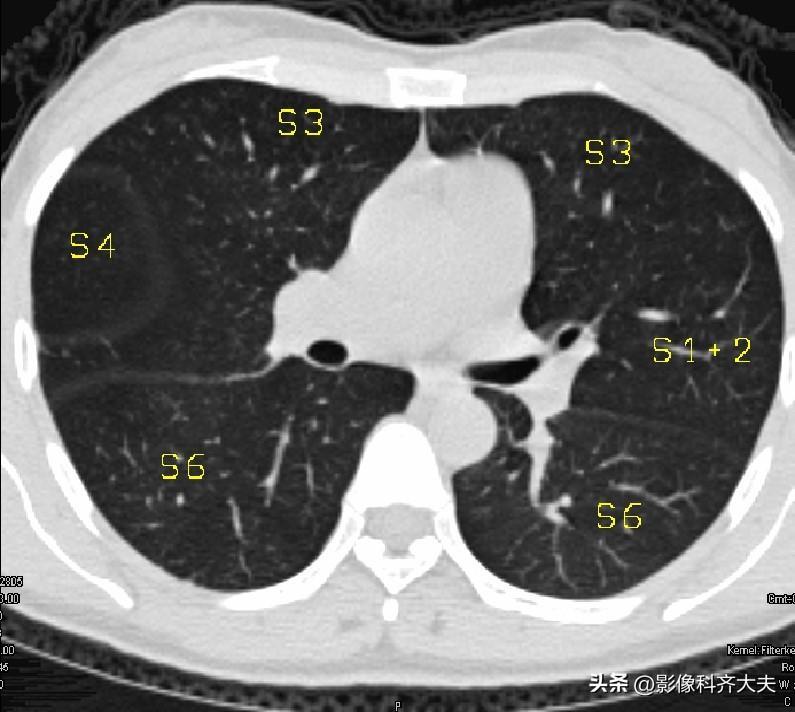

图10-隆突下2cm层面

▲S4:右中叶外段/左舌上段